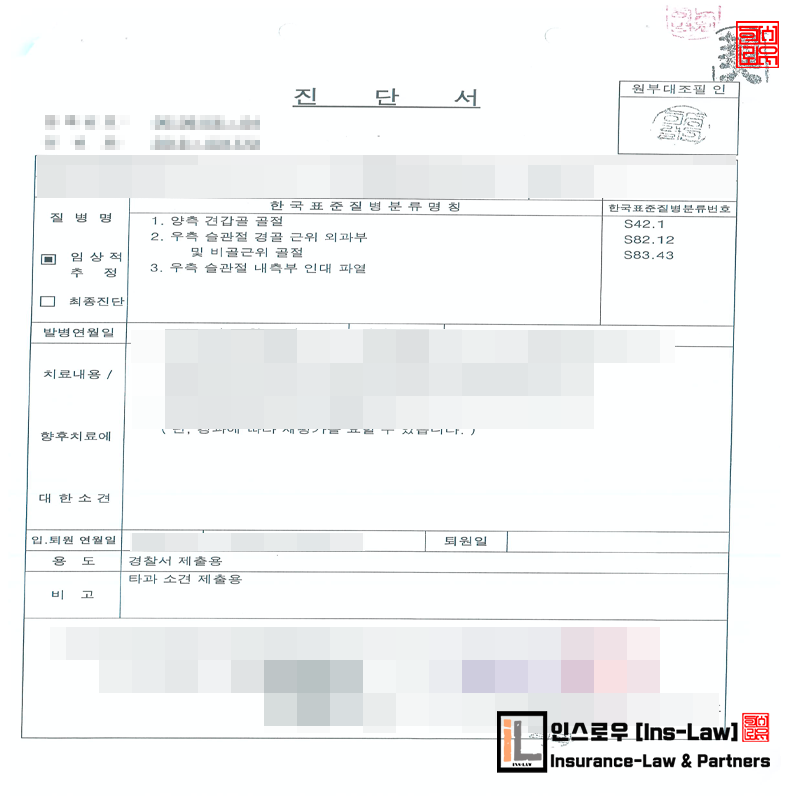

(주상병)

① 좌측 상견갑 신경 및 액와 신경손상

② 우측 견갑골 체부 골절

③ 좌측 견갑골 관절와 주위 복합골절 후 불유합상태

■ 병 명

Lt shoulder pain

보행중 치에 치였으며 견갑골 골절

견갑골은 불유합 및 거상 장애

■ 진단명

Fraxture of glenoid cavity and neck scapula, closed